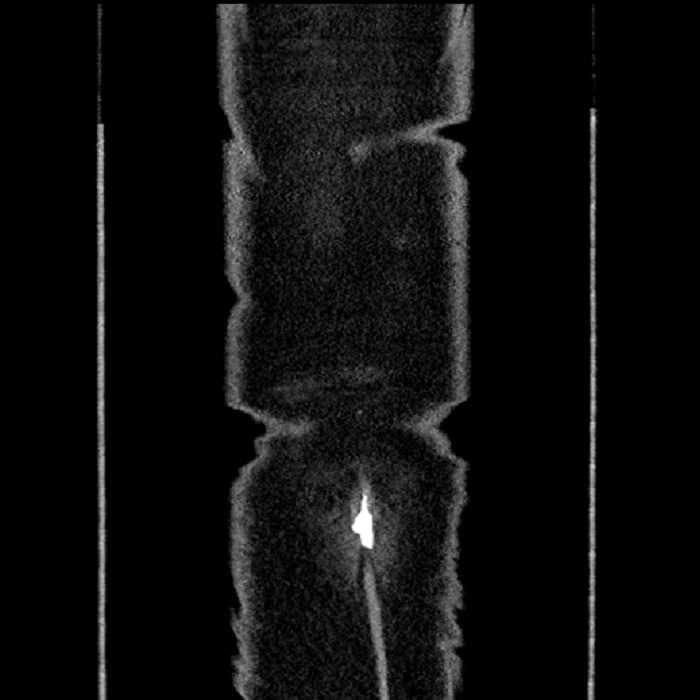

Hepatic abscess showing the double target sign with low density internally surrounded by a thin inner enhancing rim (red arrow) and ill-defined outer low density rim (yellow arrow). Blue arrow indicates an internal septation. Red arrows: additional smaller subcapsular abscesses. Red arrow: focal contained perforation associated with diverticulitis.